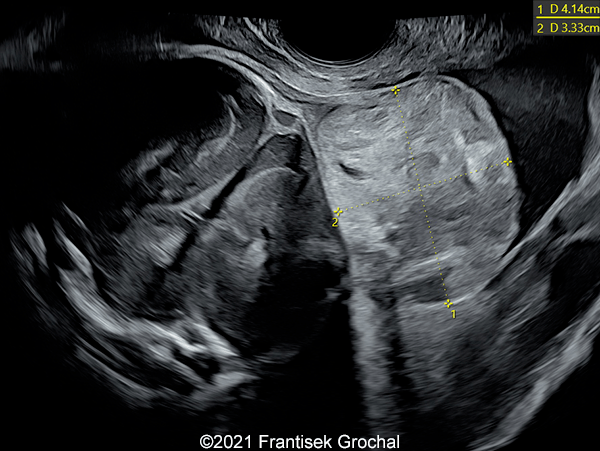

Case Report: A 24-year-old secundigravida, primipara presented to our office at 24 weeks and 6 days of her pregnancy due to a right-sided cranial parieto-occipital mass of the fetus. We obtained the following images.

Our ultrasound images at 24 weeks, 6 days show a highly vascularized, mostly solid mass measuring 58 x 45 x 34mm in the right-parieto-occipital subcutaneous region. Vascular supply of the lesion could be traced to the right vertebral artery. Repeat ultrasound exams done later in pregnancy demonstrated that the size of the mass remained stable with overall mass volume about 58 cm³.